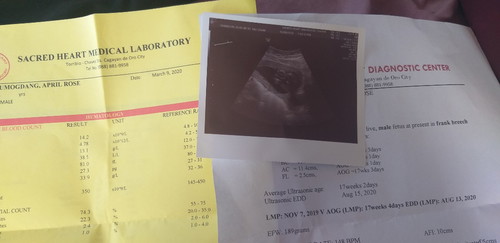

gender ultrasound

17weeks and 4days ? Kita na yung gender and its a Boy ?